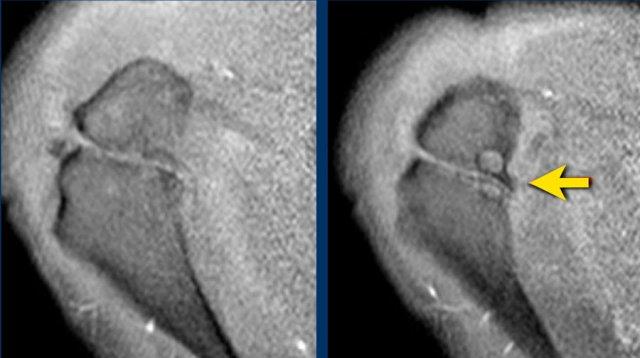

Hình ảnh là MRI khớp có thuốc tương phản từ chuỗi xung T1W xóa mỡ mặt phẳng coronal.

Hình ảnh cho thấy rách bán phần mặt khớp đoạn xa gân cơ trên gai hay còn gọi là rách bờ viền, cũng được gọi là tổn thương PASTA – bong gân bán phần mặt khớp gân cơ trên gai.

Đây là tổn thương PASTA ở một bệnh nhân khác.

Hình ảnh

Hình minh họa và MRI khớp có thuốc tương phản từ chuỗi xung T1 xóa mỡ mặt phẳng coronal.